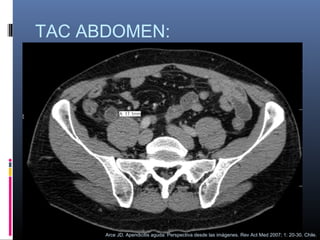

TAC ABDOMEN:

Arce JD. Apendicitis aguda: Perspectiva desde las imágenes. Rev Act Med 2007; 1: 20-30. Chile.

Criterios tomográficos

 Diámetro mayor de 7 mm.

 Lumen

apendicular

contenido líquido.

dilatado

 Alteración de los planos grasos.

con

 Engrosamiento de las paredes del

ciego e ileon terminal (signo de la barra

cecal y de la punta de flecha).

apéndice que se impregnan con el

medio de contraste IV.

 Apendicolito

 Masa de partes blandas en flanco o fosa

ilíaca derecha

 Restos apendiculares

 Aire extraluminal

 Ascitis

 Colecciones líquidas intraperitoneales

(simples o complejas)

 Obstrucción intestinal

 Derrame pleural